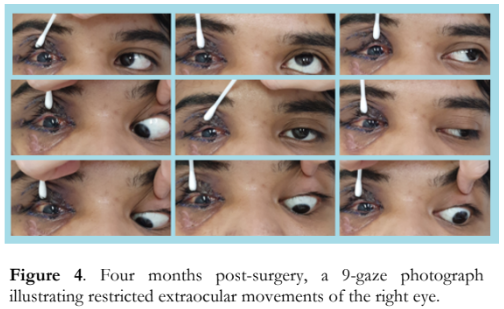

Four months after the surgery, visual acuity of the right eye improved to 20/50 while ocular motility showed very minimal improvement on left gaze (Figure 4). The right upper eyelid remained ptotic and the right pupil was still 5 mm dilated, without relative afferent pupillary defect (RAPD) noted. The rest of the eye findings remained unchanged.